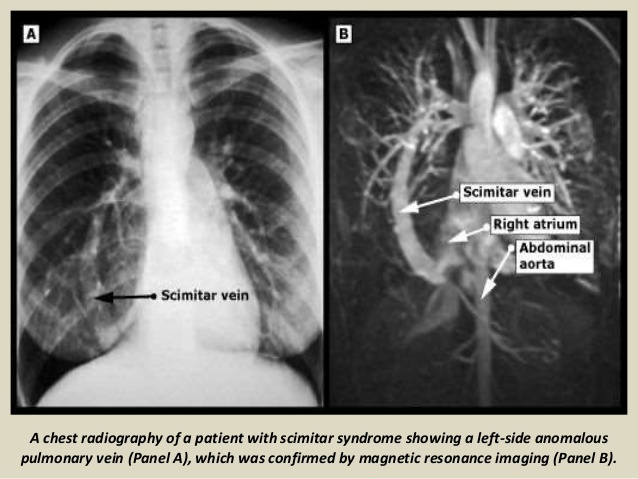

hypoplastic right lung with ipsilateral mediastinal shift and vertical vein (PAPVR of a portion or all of the right lung)

Scimitar Syndrome

Could also px as: bilobed right lung with a hyparterial right main and upper lobe bronchus

If systemic arteries from the abdomen are found to supply a portion of the lung, the resultant “complete” entity is also known as the scimitar syndrome.

**hyparterial bronchus–bronchus is below the PA (normal on the L but not the R)